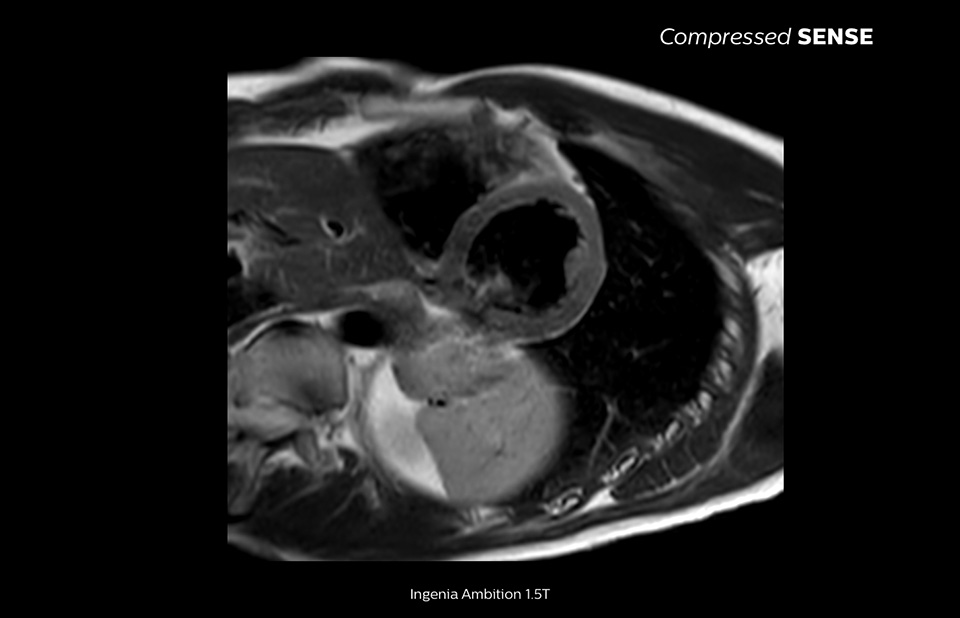

A paradigm shift in productivity

Learn more about the main principles of Compressed SENSE MRI software and how it introduces a paradigm shift in productivity. Compressed SENSE was designed around image quality, and it can accelerate scans, increase spatial resolution and enhance the patient experience for clinical MR imaging.